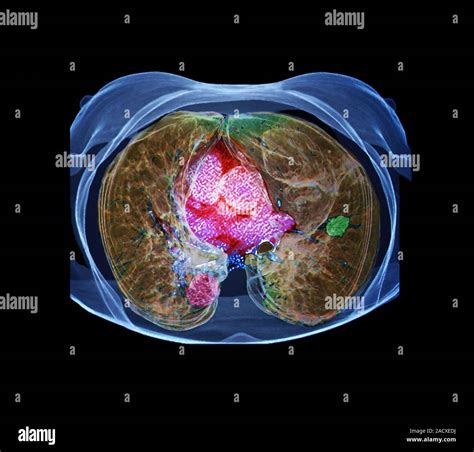

In the field of radiology, the density of tissues dictates how they appear on an x-ray image. Soft tissues and blood vessels often lack the necessary contrast to be seen distinctly without assistance. This is where Iodine Contrast proves invaluable. Because iodine has a high atomic number, it is highly efficient at absorbing x-rays, which causes those specific areas to appear bright white on a digital scan. This visual “pop” helps clinicians track blood flow, identify blockages, and characterize the margins of tumors or inflammation.

When injected into the bloodstream, the agent travels through the circulatory system, highlighting the arterial and venous anatomy. This is particularly crucial in emergency scenarios, such as detecting pulmonary embolisms or assessing internal bleeding after trauma. Furthermore, the substance is cleared by the kidneys, which provides a secondary benefit: the imaging process can simultaneously offer insights into how well the patient's renal system is functioning.